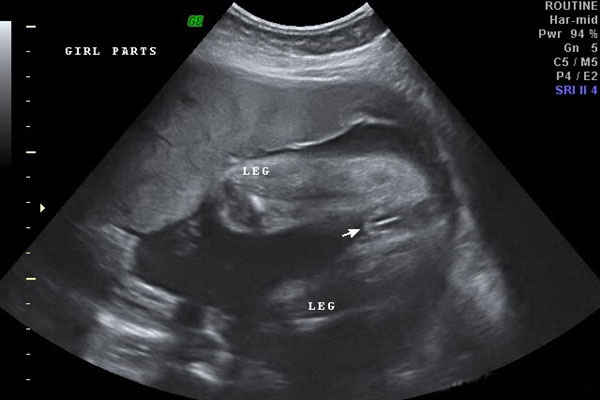

《16周女宝清晰B超图分享:三条线、凸起、字母是明显特征》对于胎儿性别的话题,一直都是准妈妈们讨论的热点,在网上很早就有宝妈分享过经验,比如孕期症状等土方法看男女,包括分享一些有关成功生女孩的症状和孕期反应等。但其实仅凭这些也是不准的,准确率最高的还是b超,如果b超的位置好、仪器先进、胎儿月份合适,通过b超是可以看到宝宝性别的,通常B超单上三条线、凸起、英文字母是最明显的特征。Wjs试管婴儿资讯平台_全面而体贴的中文母婴孕育网

大家可以看到图中女宝的生殖器结构,上面有类似于线条的一杠,这就是女宝胎儿的外生殖器结构了,也就是我们所说的大小阴唇,有的时候b超看到是一条线,大多时候是三条,有这一点,女宝就更好确认了。孕周大了之后,这个时候性别特征不仅很明显,而且非常清晰好分辨,看男女基本都是十有八九的事情;Wjs试管婴儿资讯平台_全面而体贴的中文母婴孕育网

在B超检查单上通常会有YX英文字母,准妈妈在16周做完B超检查后,拿到检查单子,可以看看B超图像上是不是最顶部有一橫行,橫行中间会有显示Y或X的字母,如果是Y就代表你怀的是女孩,X就是男孩。有的地方很严格,B超单上可能没有;Wjs试管婴儿资讯平台_全面而体贴的中文母婴孕育网

在B超检查单上,男宝宝的性别特征比较明显,常常“凸起的东西”是特有的标志,在做B超的时候可以看到胎儿生殖器官这里,如果有小小的突起的话,生男宝宝的可能性较大,相反,生女宝宝的可能小较小。Wjs试管婴儿资讯平台_全面而体贴的中文母婴孕育网